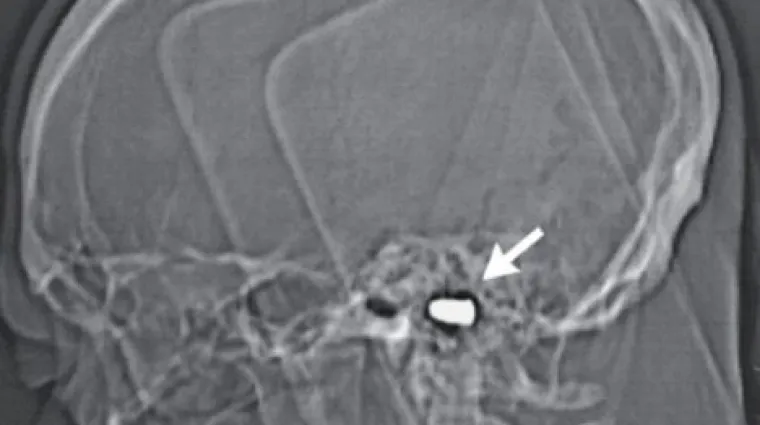

Nevjerojatan slučaj ranjavanja dogodio se u tijekom malonogometnog turnira u sarajevskom naselju Boljakov Potok, javlja Dnevni Avaz. Naime, golmana jedne momčadi je u glavu pogodio zalutali metak pištolja "Crvena zastava" kalibra devet milimetara, ostavši pritom u lubanji.

Nesretni 51-godišnji Duško Krtalica čak je s metkom u glavi nastavio braniti za svoju momčad misleći da je glavom udario u vratnicu. Zanimljivo, na utakmici je primio tek jedan pogodak.

Pošto je dvoboj završio Duško je primijetio da mu se ruke otkazuju i da ima poteškoća s govorom te je brzo prevezen u bolnicu. Tamo su šokirani liječnici ustanovili kako je 51-godišnjak cijelo to vrijeme imao metak u glavi.

Naravno, doktori su odmah obavijestili nadležne službe o ovom incidentu pa je policija krenula u opsežnu potragu za počiniteljem. Ispostavilo se da je hitac ispaljen na jednoj od tri svadbe koje su toga dana održane u spomenutom sarajevskom naselju zbog čega je i privedena jedna osoba.